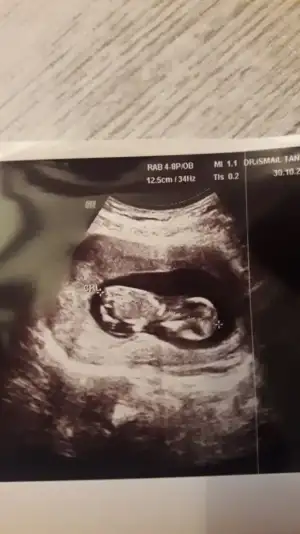

Merhaba bizim bebiş ters duruyor secde pozisyonunda ultrasona göre 12+3 benim bebişim içinde bir tahminde bulanabilirmisiniz rica etsem.

Cinsiyetimiz nedir sizce :)